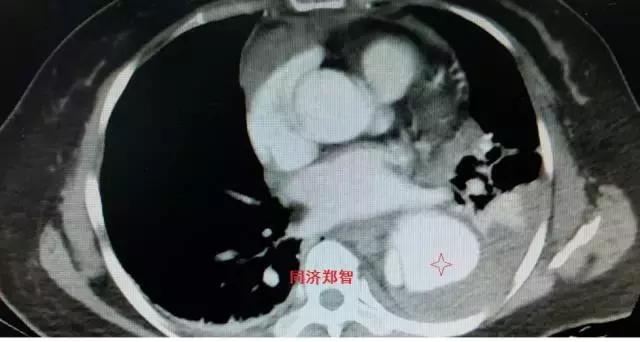

病例三

胸部平扫CT提示胸降动脉增宽(红色星形标记),CTA证实B型主动脉夹层伴降主动脉夹层动脉瘤形成。